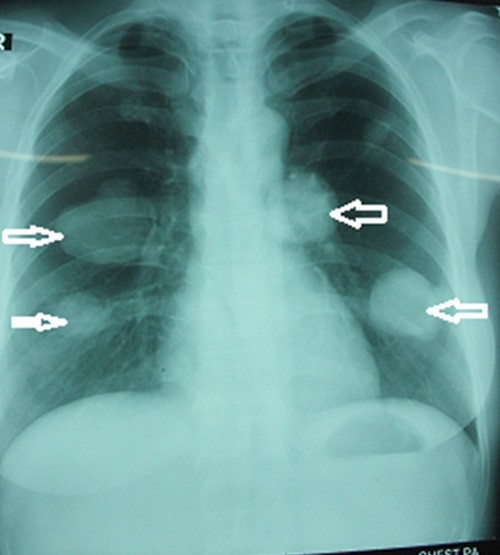

Bệnh nhân nhập viện Lao phổi Trung ương để điều trị, kết quả chụp X-quang cho thấy bệnh nhân có 4 khối u khổng lồ trên phổi.Đây là trường hợp rất nguy hiểm, bởi mỗi bên phổi bệnh nhân có 2 u. Trường hợp này không thể phẫu thuật vì nếu cắt sẽ phải cắt toàn bộ phổi và bệnh nhân sẽ tử vong ngay. Các bác sĩ đã chọc dò hút dịch để kiểm tra thì thấy hàng nghìn đầu sán ở mỗi ổ.

Loại sán chó chỉ có thể nhìn bằng kính hiển vi, có thể gây tử vong cho người bệnh. Ảnh chụp phổi bệnh nhân là cán bộ y tế bị sán chó làm tổ trong 2 bên phổi. |

"Bệnh nhân này là cán bộ y tế, hiện vẫn đi làm bình thường. Tuy nhiên, do vẫn còn ho ra máu, kết quả xét nghiệm vẫn còn sán dây chó, nên bệnh nhân vẫn phải tiếp tục uống thuốc”, TS Đề chia sẻ.